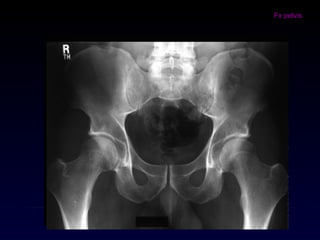

En fractura de

fémur siempre

Rx AP de pelvis

En Fx de cadera

siempre Rx

AP de pelvis

• #7 Por otro lado existe algo que hemos denominado la “regla de las dos”, que hace referencia a parámetros que siempre se deben tener en cuenta, de acuerdo al segmento evaluado; asi tenemos entonces: En toda lesión de huesos largos se debe solicitar una radiografía que incluya una articulación por encima y por debajo de la lesión diafisiaria En manos y pies no debemos olvidar solicitar radiografia anteroposterior y oblicua, cuando estemos evaluando metacarpianos, o falanges proximales, y para el caso de los pies metatarsianos y antepie. En los niños son muy útiles las imágenes comparativas, ya que las líneas de crecimiento o fisis y los nucleos de osificación secundarios pueden fácilmente confundirse en la radiografía con una lesión tipo fractura, sin existir, en el escenario del trauma de una extremidad con dolor. Siempre que sospechemos de una fractura de cadera, con o sin desplazamiento clínicamente evidente, es necesario solicitar una radiografía anteroposterior (AP) de pelvis y lateral de la cadera que estamos evaluando; esto por que algunas fracturas con trazos sutiles y no desplazadas no son fácilmente identificables, a menos que tengamos un parámetro para comparar, y en este caso seria la cadera contralateral. Además en algunas ocasiones, en las que a pesar de una clínica muy clara de lesión en la cadera no es posible ver la lesión en las radiografías convencionales, se hace necesario solicitar imágenes con tracción longitudinal y rotaciones, maniobra que se realizad durante la toma de la radiografía. Toda fractura diafisiaria de femur, ademas de incluir la rodilla en la evaluación imaginológica, también debe incluir una radiografía AP de pelvis. Ejemplos: